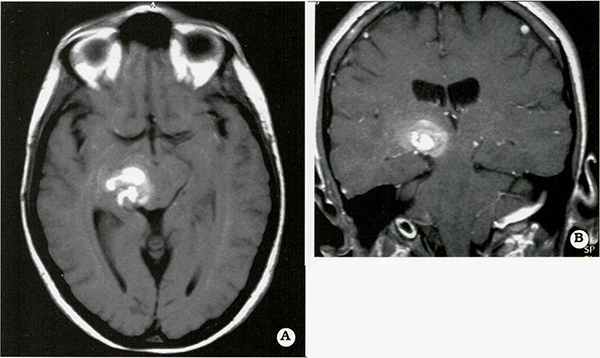

Los cavernomas pueden presentarse en forma solitaria o múltiple. En el síndrome de cavernomatosis familiar se han encontrado múltiples lesiones en un 50% al 73% de los casos (Fig. 1) comparados con los casos esporá dicos que presentan lesiones múltiples en menos de un 33%20,39,41,47,55,60,64.

Fig. 1.

Paciente con cavernomatosis familiar múltiple. Las imágenes axial (A) y coronal (B) por resonancia magnética permiten apreciar las lesiones de densidad heterogénea características típicas de estas malfor­maciones.